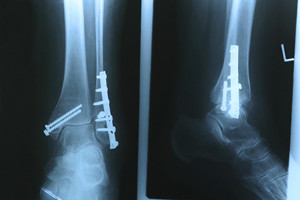

stress fracture is defined as a hairline fracture that is generally the result of stress the bones endure from high impact activities such as running.  Because of this, the feet and lower legs are often susceptible to developing a stress fracture.  It is beneficial to implement adequate recovery procedures, despite the fact that many athletes choose to run through the pain and discomfort. A full recovery often begins with refraining from running for approximately four to six weeks, in addition to performing strengthening and flexibility exercises. If the stress fracture is severe, a boot may be worn for stability as the healing process occurs. If you have pain in your foot that increases gradually, it is strongly suggested that you visit a podiatrist who can diagnose and treat any potential stress fractures.

Stress fractures occur in the foot and ankle when muscles in these areas weaken from too much or too little use.  The feet and ankles then lose support when walking or running from the impact of the ground. Since there is no protection, the bones receive the full impact of each step. Stress on the feet can cause cracks to form in the bones, thus creating stress fractures.